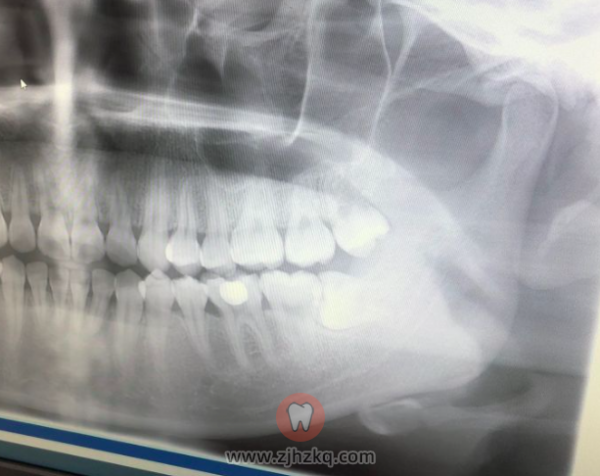

据说补充维c有好处,我现在吃不了蔬菜水果就买了些维c片。下周还要去拆线。对了,我的牙片这样,完全横长,另一侧还有一颗差不多的,位置更低,愁啊